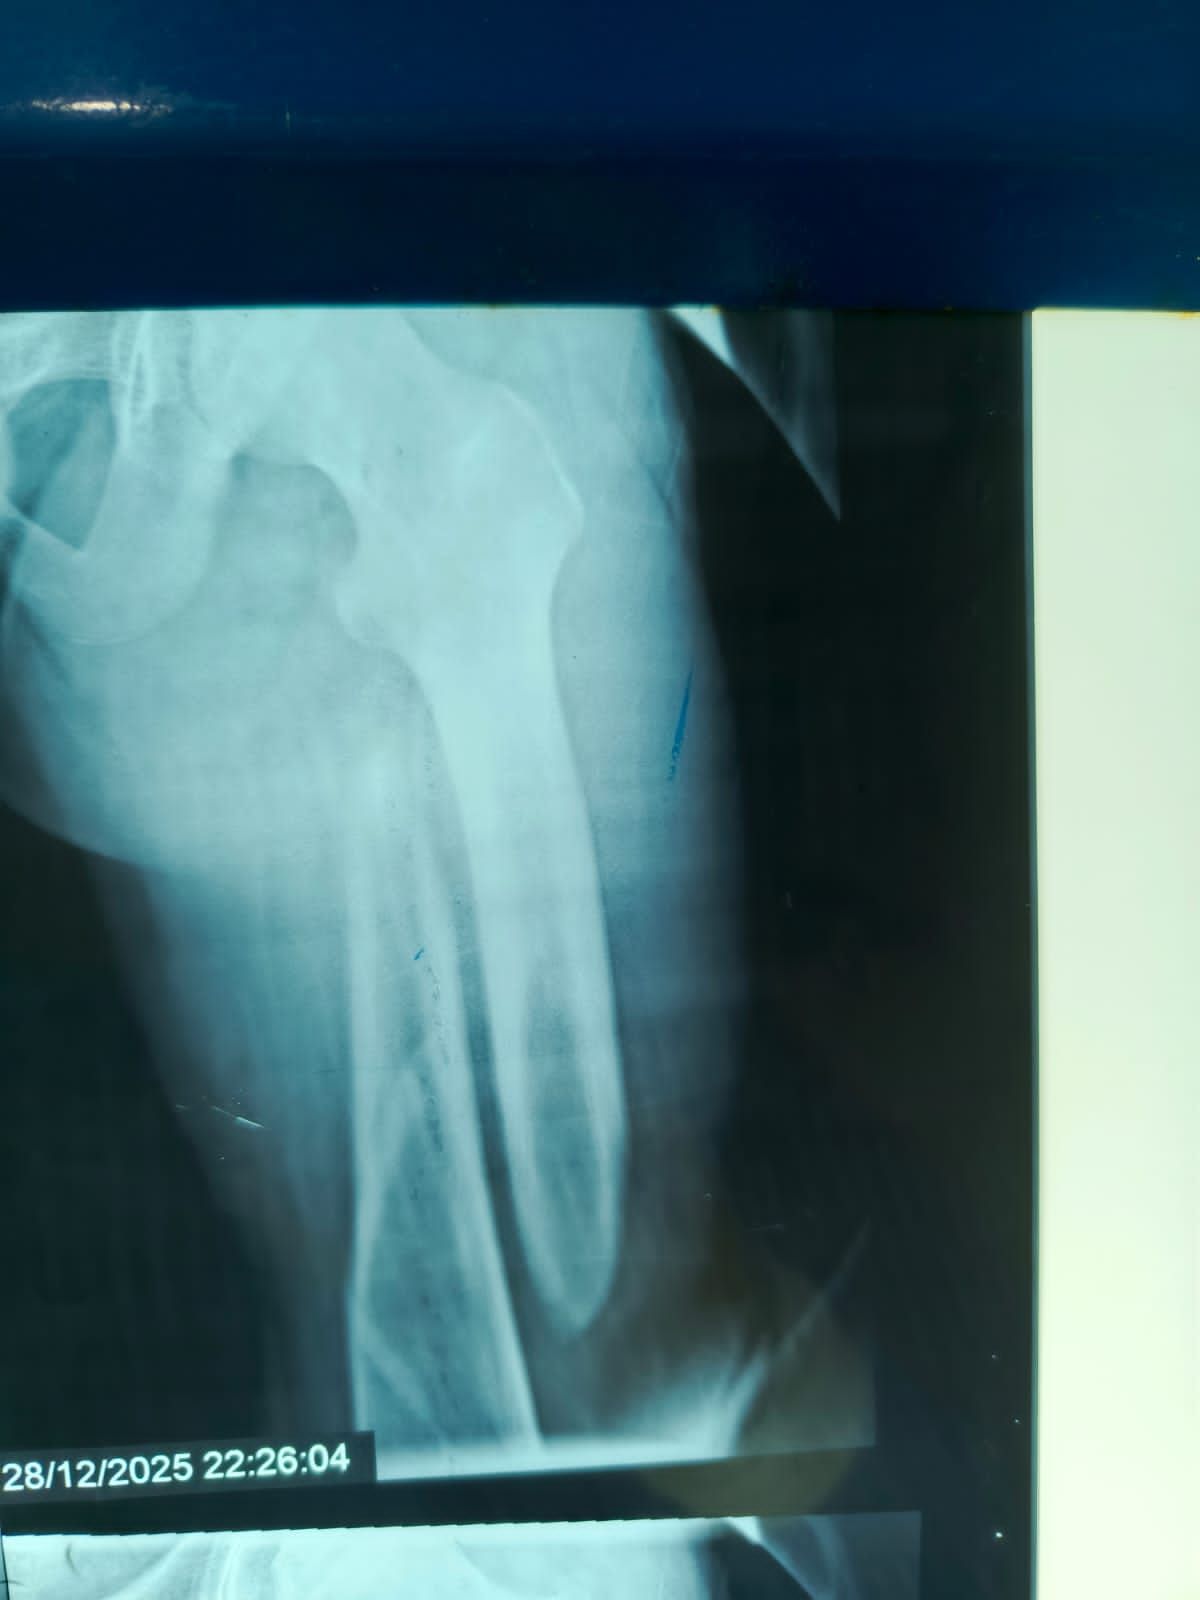

نجح الفريق الطبي بقسم الطوارئ والعمليات بمستشفى مغاغة العام بمحافظة المنيا ، في إنقاذ شاب يبلغ من العمر 16 عامًا، تعرض لحادث مروري مروع أسفر عن كسر مفتت متعدد المواضع بعظمة الفخذ الأيسر، وذلك من خلال إجراء جراحة متقدمة باستخدام تقنية المسمار النخاعي التشابكي في زمن قياسي.

وفور وصول المصاب إلى قسم الطوارئ، جرى التعامل الفوري معه، وتم اتخاذ القرار الطبي العاجل بإجراء جراحة المسمار النخاعي التشابكي دون فتح موضع الكسر، بما يتوافق مع أحدث البروتوكولات الطبية العالمية. واستغرقت العملية نحو ساعتين ونصف فقط، غادر بعدها المريض غرفة العمليات في حالة مستقرة.

وتميزت الجراحة بعدة مزايا، من بينها : جروح جراحية محدودة للغاية ، وتقليل فرص النزيف والعدوى إلى أدنى حد ، وتسريع معدلات التئام العظام مقارنة بالطرق التقليدية.